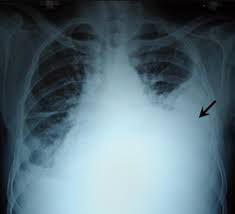

Massive hemothorax symptoms

Symptoms include: Shortness of breath. Rapid, shallow breathing. Chest pain. Low blood pressure (shock) Pale, cool and clammy skin. Rapid heart rate. Restlessness. Anxiety.